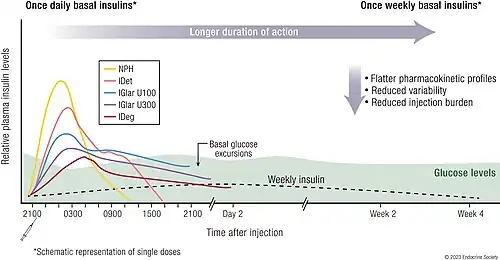

Ultralong-acting

Insulin degludec

Insulin degludec is an ultralong-acting basal insulin analogue developed by Novo Nordisk.[172] Ultralong-acting insulins are a kind of insulin that can work up to a week.[173] It is administered through subcutaneous injection to assist in controlling blood sugar levels in individuals with diabetes. Its duration of action lasts up to 42 hours, which is significantly longer than other long-acting insulins, such as insulin glargine and insulin detemir, which typically last 18 to 26 hours. This makes insulin degludec a once-daily basal insulin,[174][175][176] providing a steady insulin level, in contrast to fast-acting bolus insulins. Insulin degludec is a modified form of insulin in which a single amino acid is deleted compared to human insulin. It is also conjugated to hexadecanedioic acid via a gamma-L-glutamyl spacer at the amino acid lysine at position B29.[175]

Insulin icodec

Insulin icodec is a medication used to enhance glycemic control in individuals with diabetes.[178] It is an ultralong-acting basal insulin analogue developed by Novo Nordisk.[179] The analog has a plasma half-life exceeding eight days, which is significantly longer than the 25-hour half-life of insulin degludec, the previously longest-acting insulin analogue. Insulin icodec functions as a once-weekly basal insulin.[178]

Structurally, insulin icodec consists of two peptide chains connected by a disulfide bridge, similar to insulin. However, it includes a C20 fatty diacid-containing side chain to enable strong, reversible albumin binding. Additionally, three amino acid substitutions enhance molecular stability, reduce insulin receptor binding, and slow clearance, collectively extending its duration of action.[180]

Insulin icodec received approval for medical use in Canada in March 2024.[179] In the same month, the Committee for Medicinal Products for Human Use (CHMP) of the European Medicines Agency (EMA) issued a positive opinion, recommending marketing authorization for insulin icodec.[178] Subsequently, insulin icodec was approved for medical use in the European Union in May 2024.[180] Insulin icodec is currently marketed by Novo Nordisk under the name Awiqli (pronounced A-week-ly).[181]